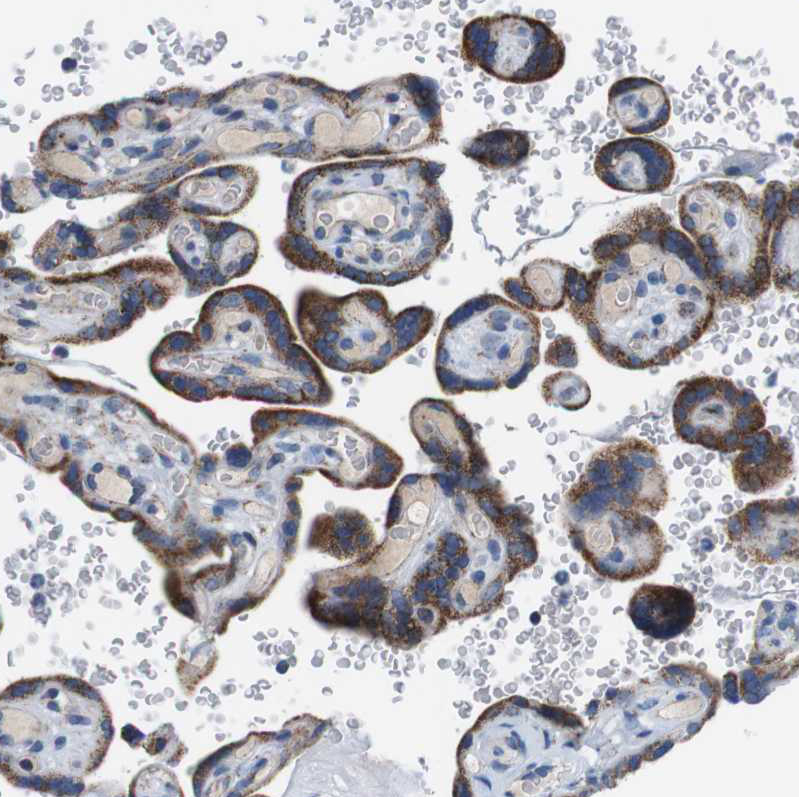

Immunohistochemical staining of human ovary shows moderate cytoplasmic/ membranous positivity in oocytes.